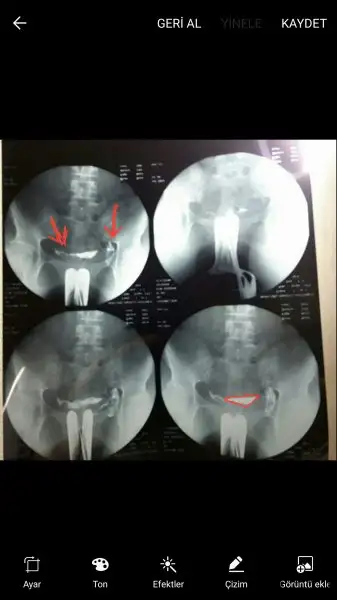

Canim ben bisey anlamiyorum bana isaretleyip yollarmisin sana zahmet rahim neresi tüp neresi normal mi sence benim filmimRabbim herkesin rahmini Şekil şekil yaratmış Valla çok değişik

bende bi hftadır sizin filmlerden öğrendim biraz ilaç yumurtalıklara ulaşmışsa tüpler açık oluo ortada üçgen gibi gözüken rahim siyah benekler varsa yapışıklıkSen yine anliyosun ben hic anlamiyorum rahim hangisi tupler neresi acik olduğunu nere anliyosunuz hiç bilmiyorum nasil arkaya yatmış ki

Bak ok işareti olan yerler tüplerden çıkan sıvı, üçgen çizdiğim yer de rahimSen yine anliyosun ben hic anlamiyorum rahim hangisi tupler neresi acik olduğunu nere anliyosunuz hiç bilmiyorum nasil arkaya yatmış ki

Rahim su siyah olan bosluk mu tüp neresi peki

Cnm benim telde işaretleyemiyorum ama ilaç yumurtalıklara kadar gitmiş belliki kanallar açık ama rahim Şekli nette gördüğüm birçok filmden farklı.tabiki biz uzman değiliz sadece karşılaştırma yapıyoruz.dr herşey normal Demiş zaten sen içini rahat tutCanim ben bisey anlamiyorum bana isaretleyip yollarmisin sana zahmet rahim neresi tüp neresi normal mi sence benim filmim

Bak ok işareti olan yerler tüplerden çıkan sıvı, üçgen çizdiğim yer de rahim

Bakiyorum bakiyorum bulamiyorum benim filmde üçgen yok galibabende bi hftadır sizin filmlerden öğrendim biraz ilaç yumurtalıklara ulaşmışsa tüpler açık oluo ortada üçgen gibi gözüken rahim siyah benekler varsa yapışıklık![]()

Ne kadar küçükmus bende siyah yerin tamami rahim saniyordum :)Bak ok işareti olan yerler tüplerden çıkan sıvı, üçgen çizdiğim yer de rahim